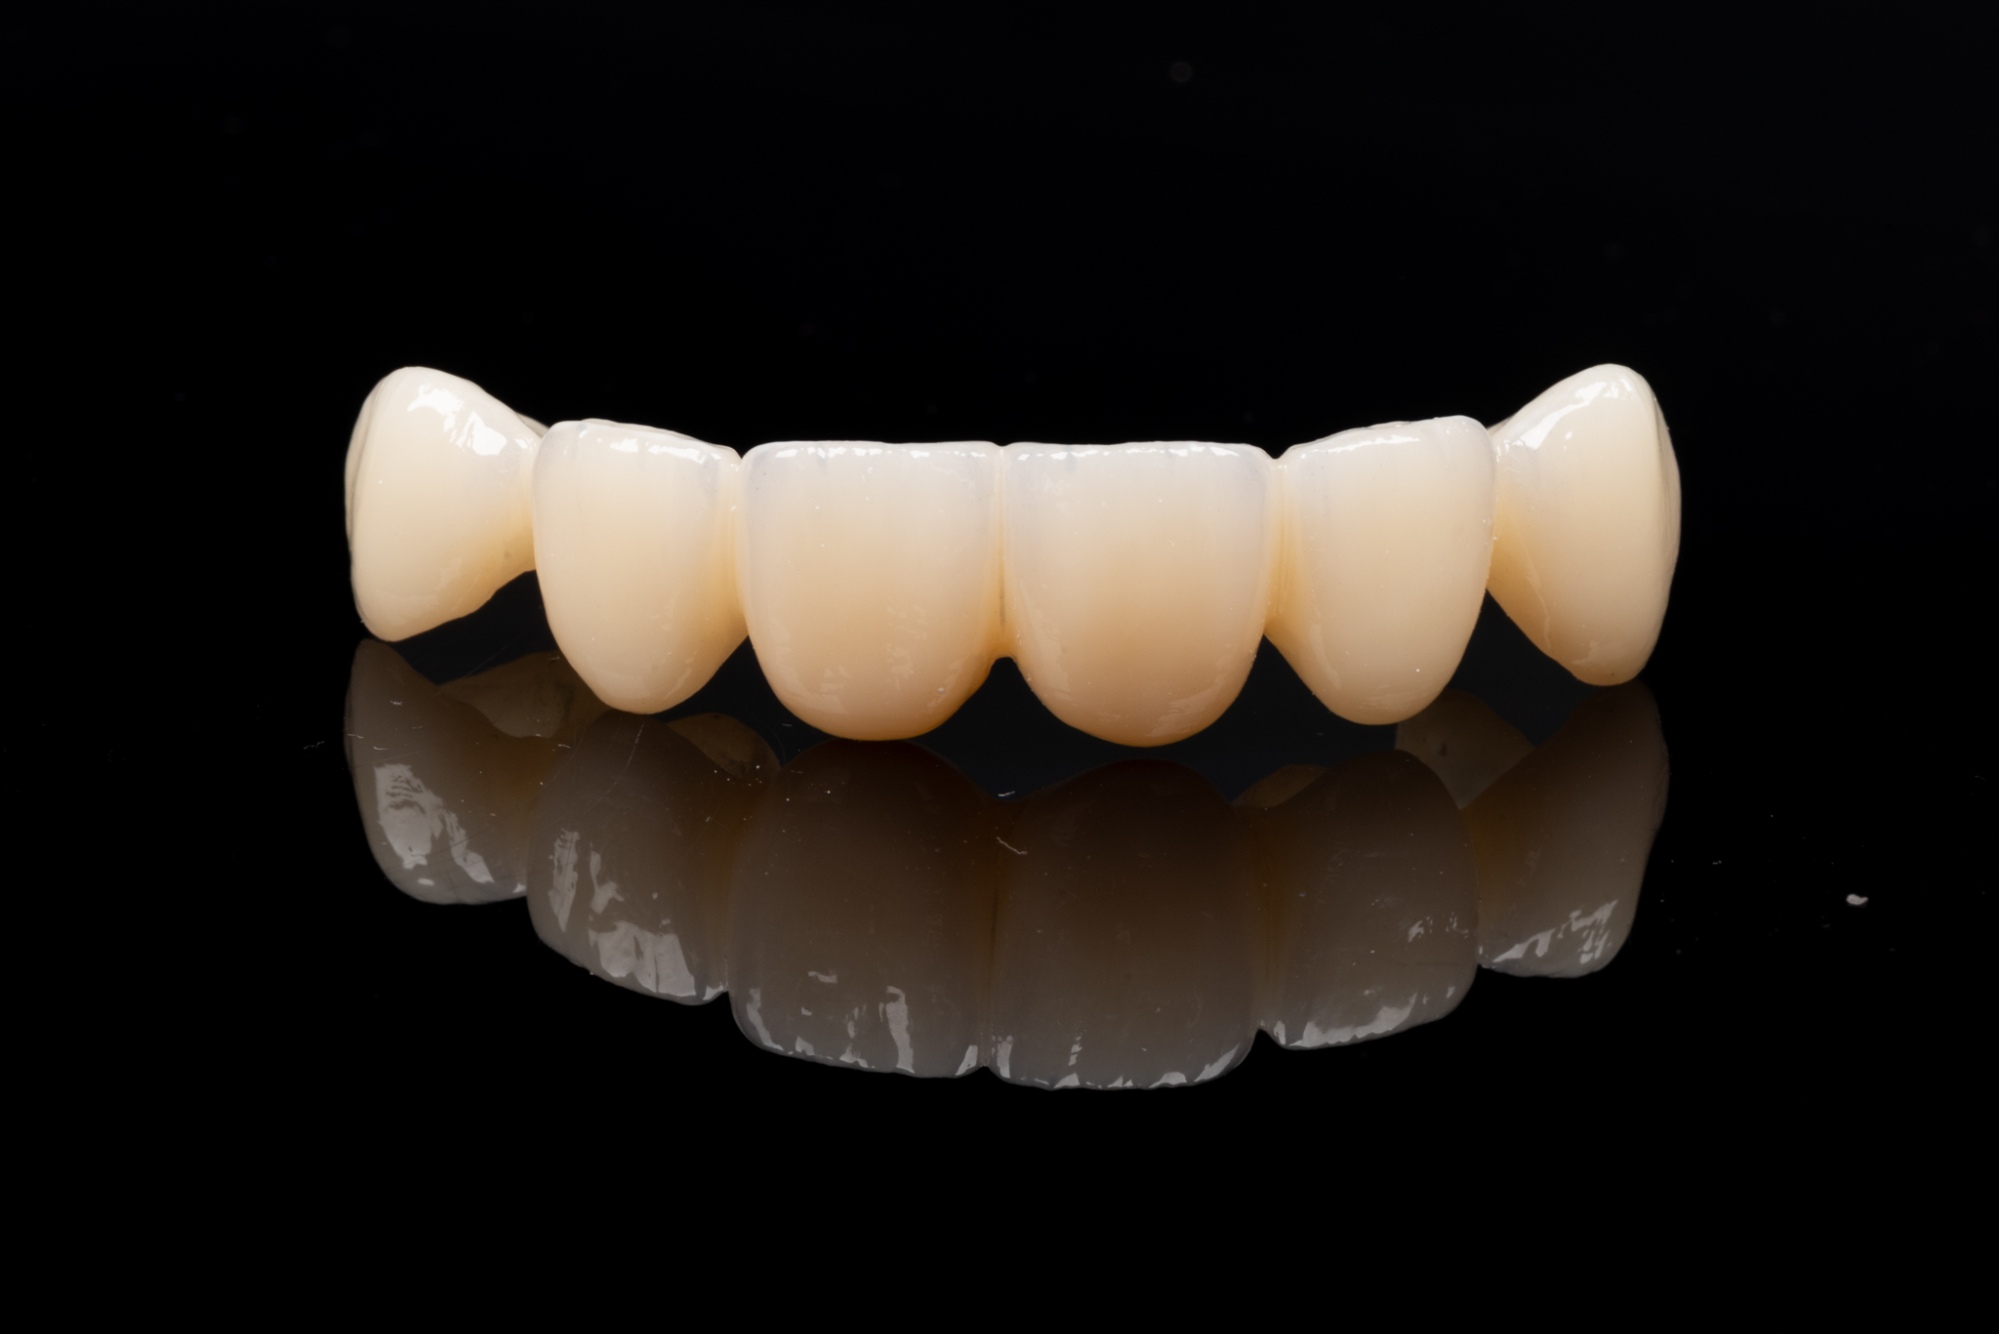

Pacjenci, którzy rozważają uzupełnienie braków w uzębieniu, często wahają się między implantem zęba a rozwiązaniami takimi jak mosty protetyczne czy protezy ruchome. Warto jednak wiedzieć, że w porównaniu z nowoczesnym leczeniem implantologicznym, zarówno most protetyczny, jak i tradycyjne protezy są rozwiązaniami kompromisowymi.

Aby uzupełnić jeden brakujący ząb za pomocą mostu protetycznego, najczęściej trzeba wykonać konstrukcję trójpunktową. Całkowity koszt takiego rozwiązania jest zbliżony do ceny implantu zęba z koroną, jednak implanty zębowe pozwalają zachować integralność sąsiednich zębów.

Założenie mostu protetycznego wymaga oszlifowania sąsiednich, często zupełnie zdrowych zębów, które stają się filarami konstrukcji. Wszczepienie implantu pozwala tego uniknąć -to uzupełnienie braków bez ingerencji w strukturę sąsiednich zębów.

Pojedynczy implant zęba z koroną funkcjonuje jak naturalny ząb i jest łatwy w oczyszczaniu. Most protetyczny, jako konstrukcja zespolona, utrudnia higienę, co może prowadzić do stanów zapalnych dziąseł i skrócenia jego żywotności.